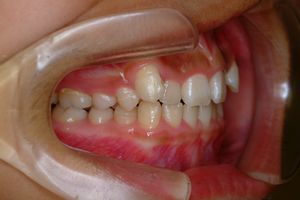

健康な小臼歯を抜いていません

矯正前                 矯正後

治療前 の 左 です 動く矢印治療後 の 左 です

治療前 の 右 です 動く矢印治療後 の 右 です